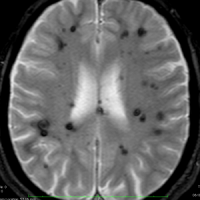

多発性海綿状血管腫 multiple cavernous hemangioma

家族性海綿状血管腫 familial cavernous hemangioma

この様な無数の海綿状血管腫を見ることがあります。多くの場合は家族性(遺伝性)の海綿状血管腫です。200個を超える海綿状血管腫があっても普通に何の障害もなく暮らしている患者さんもいます。脊髄の中にも発生しますから,脊髄のMRIもしていただきましょう。

小さな多発性の海綿状血管腫は,T2*(ティーツースター)という左の画像では見えるのですが,右にあるような普通のT1強調画像というのでははっきりみえません。

家族性多発性海綿状血管腫の患者さんは,小さな出血など生じても安易に手術を受けないようにしましょう。どの血管腫が大きくなるのかは全く予想できませんし,とても多数回の手術を受ける結果になるかもしれないからです。